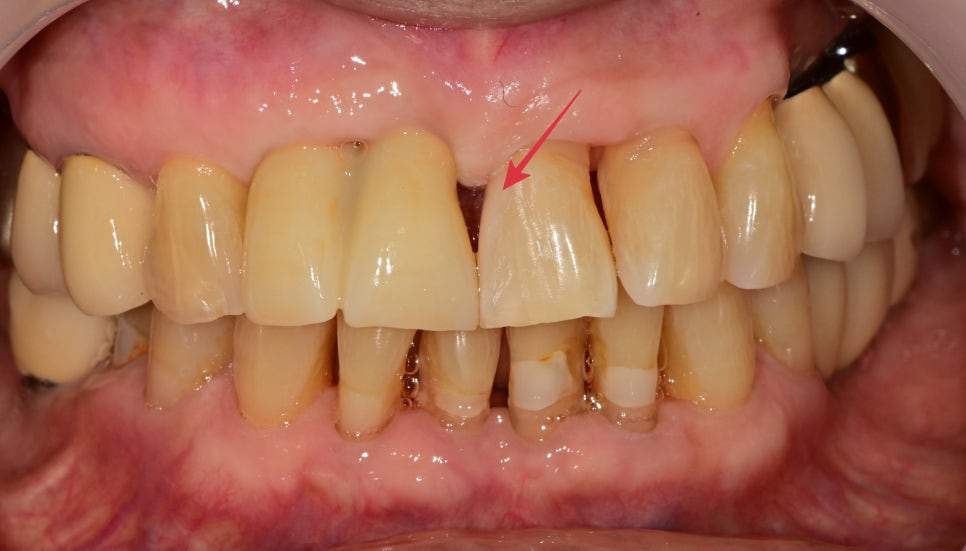

이럴 때는 임플란트 보철 시 대칭되는 치아들을 같이 보철해 주면

치아 형태를 잡기에도 좋고 비어있는 잇몸 공간을 보철에 의해 채워줄 수 있지만

환자분께서는 추가적인 잇몸 수술이나 다른 치아의 치료는 원치 않으셨고

불편한 2개의 치아만 치료를 원하셨습니다.

그렇다고 빈 공간을 메꾸기 위해 한쪽 보철만 두껍게 제작하면 오히려 더 이상해 보일 수 있습니다

다른 잇몸이나 치아를 건드리지 않고 빈 공간을 채울 수 있는 방법을 고민하다

레진을 이용해 치료해 보기로 했습니다

레진을 이용해 일단 대칭되는 치아를 빈 공간 쪽으로

풍융하게 형성해 준 후 임플란트 보철을 수정했습니다